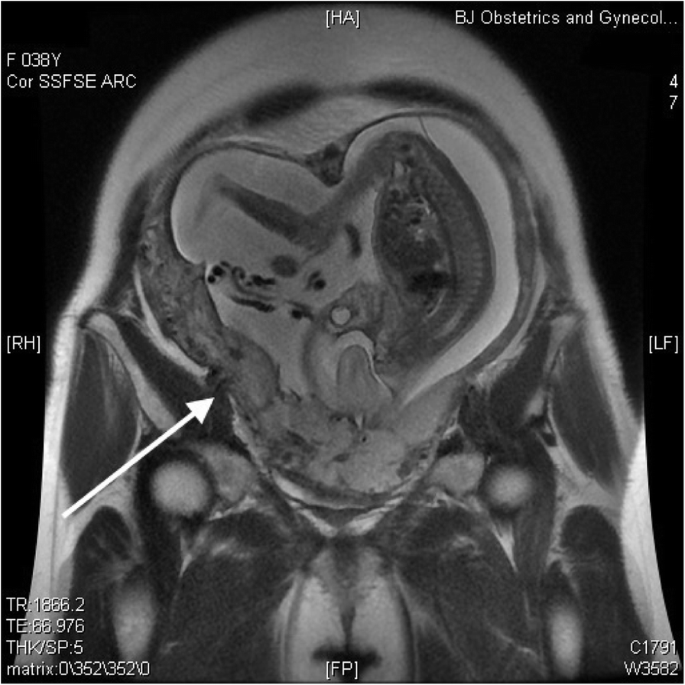

This pregnancy was naturally conceived, and the patient was under regular antenatal follow-up without the administration of progesterone. Her nuchal translucency scan was normal, and noninvasive prenatal testing indicated low risk. Magnetic resonance imaging (MRI) and ultrasound were suggestive of a posterior-anterior adherent placenta reaching the serosa with anterior myometrial thinning and partially missing at 22 weeks of gestation (Figs. 1 and 2). She reported occasional vaginal bleeding.

Regular antenatal care, color flow ultrasound, and MRI may be needed for the evaluation of an adherent placenta in patients with a history of Strassman metroplasty. Further research is needed to evaluate the optimal methods of treating postpartum hemorrhage with congenital uterine anomalies.